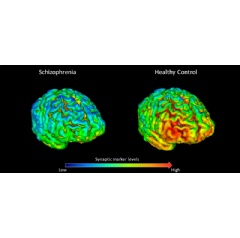

The team found lower levels of SV2A in the brains of schizophrenia patients, indicating a reduction of synapses. Certain areas exhibited significantly lower levels, such as the frontal cortex which coordinates use, recall and processing of memory, planning complex cognitive behaviour and personality expression. These findings were supported by the understanding that these areas are associated with some of the major cognitive impairments seen in schizophrenia, thus providing a potential clue that synaptic loss may underlie these problems.

“The human brain, with its approximately 100 trillion synapses, is an extraordinarily complex organ,” says Dr Ellis Chika Onwordi of the Psychiatric Imaging Group and first author of this study. “Having the means to characterise the distribution of these synapses in the living brain, and to find differences in synaptic distribution between patients with schizophrenia and healthy controls, represents a significant advance in our ability to study the neurobiology of schizophrenia.”